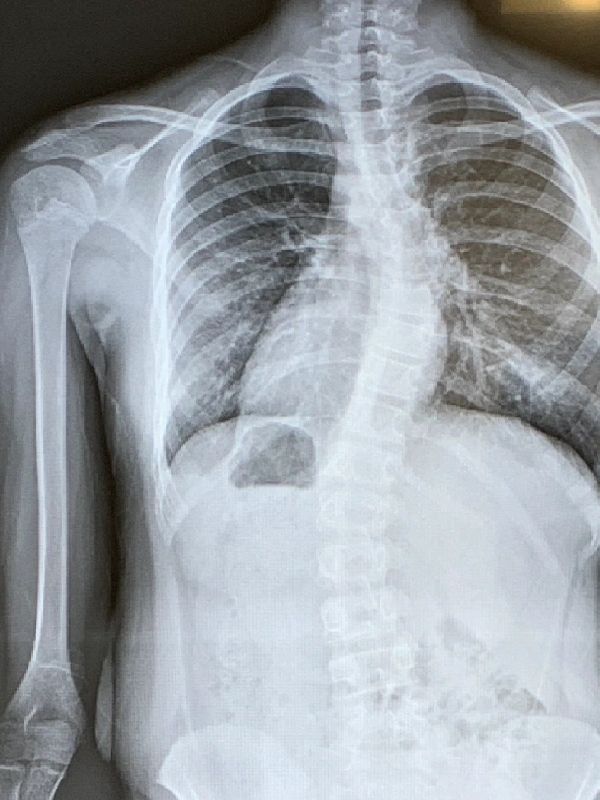

Hi and welcome to my website, My name is Livi and I am an ordinary kid, but one thing that makes me different is that I have scoliosis. Scoliosis is a curvature of the spine, which can be caused for many reasons. Scoliosis is usually found in children, but it can also be found in adults.

*An x-ray of my back is above.